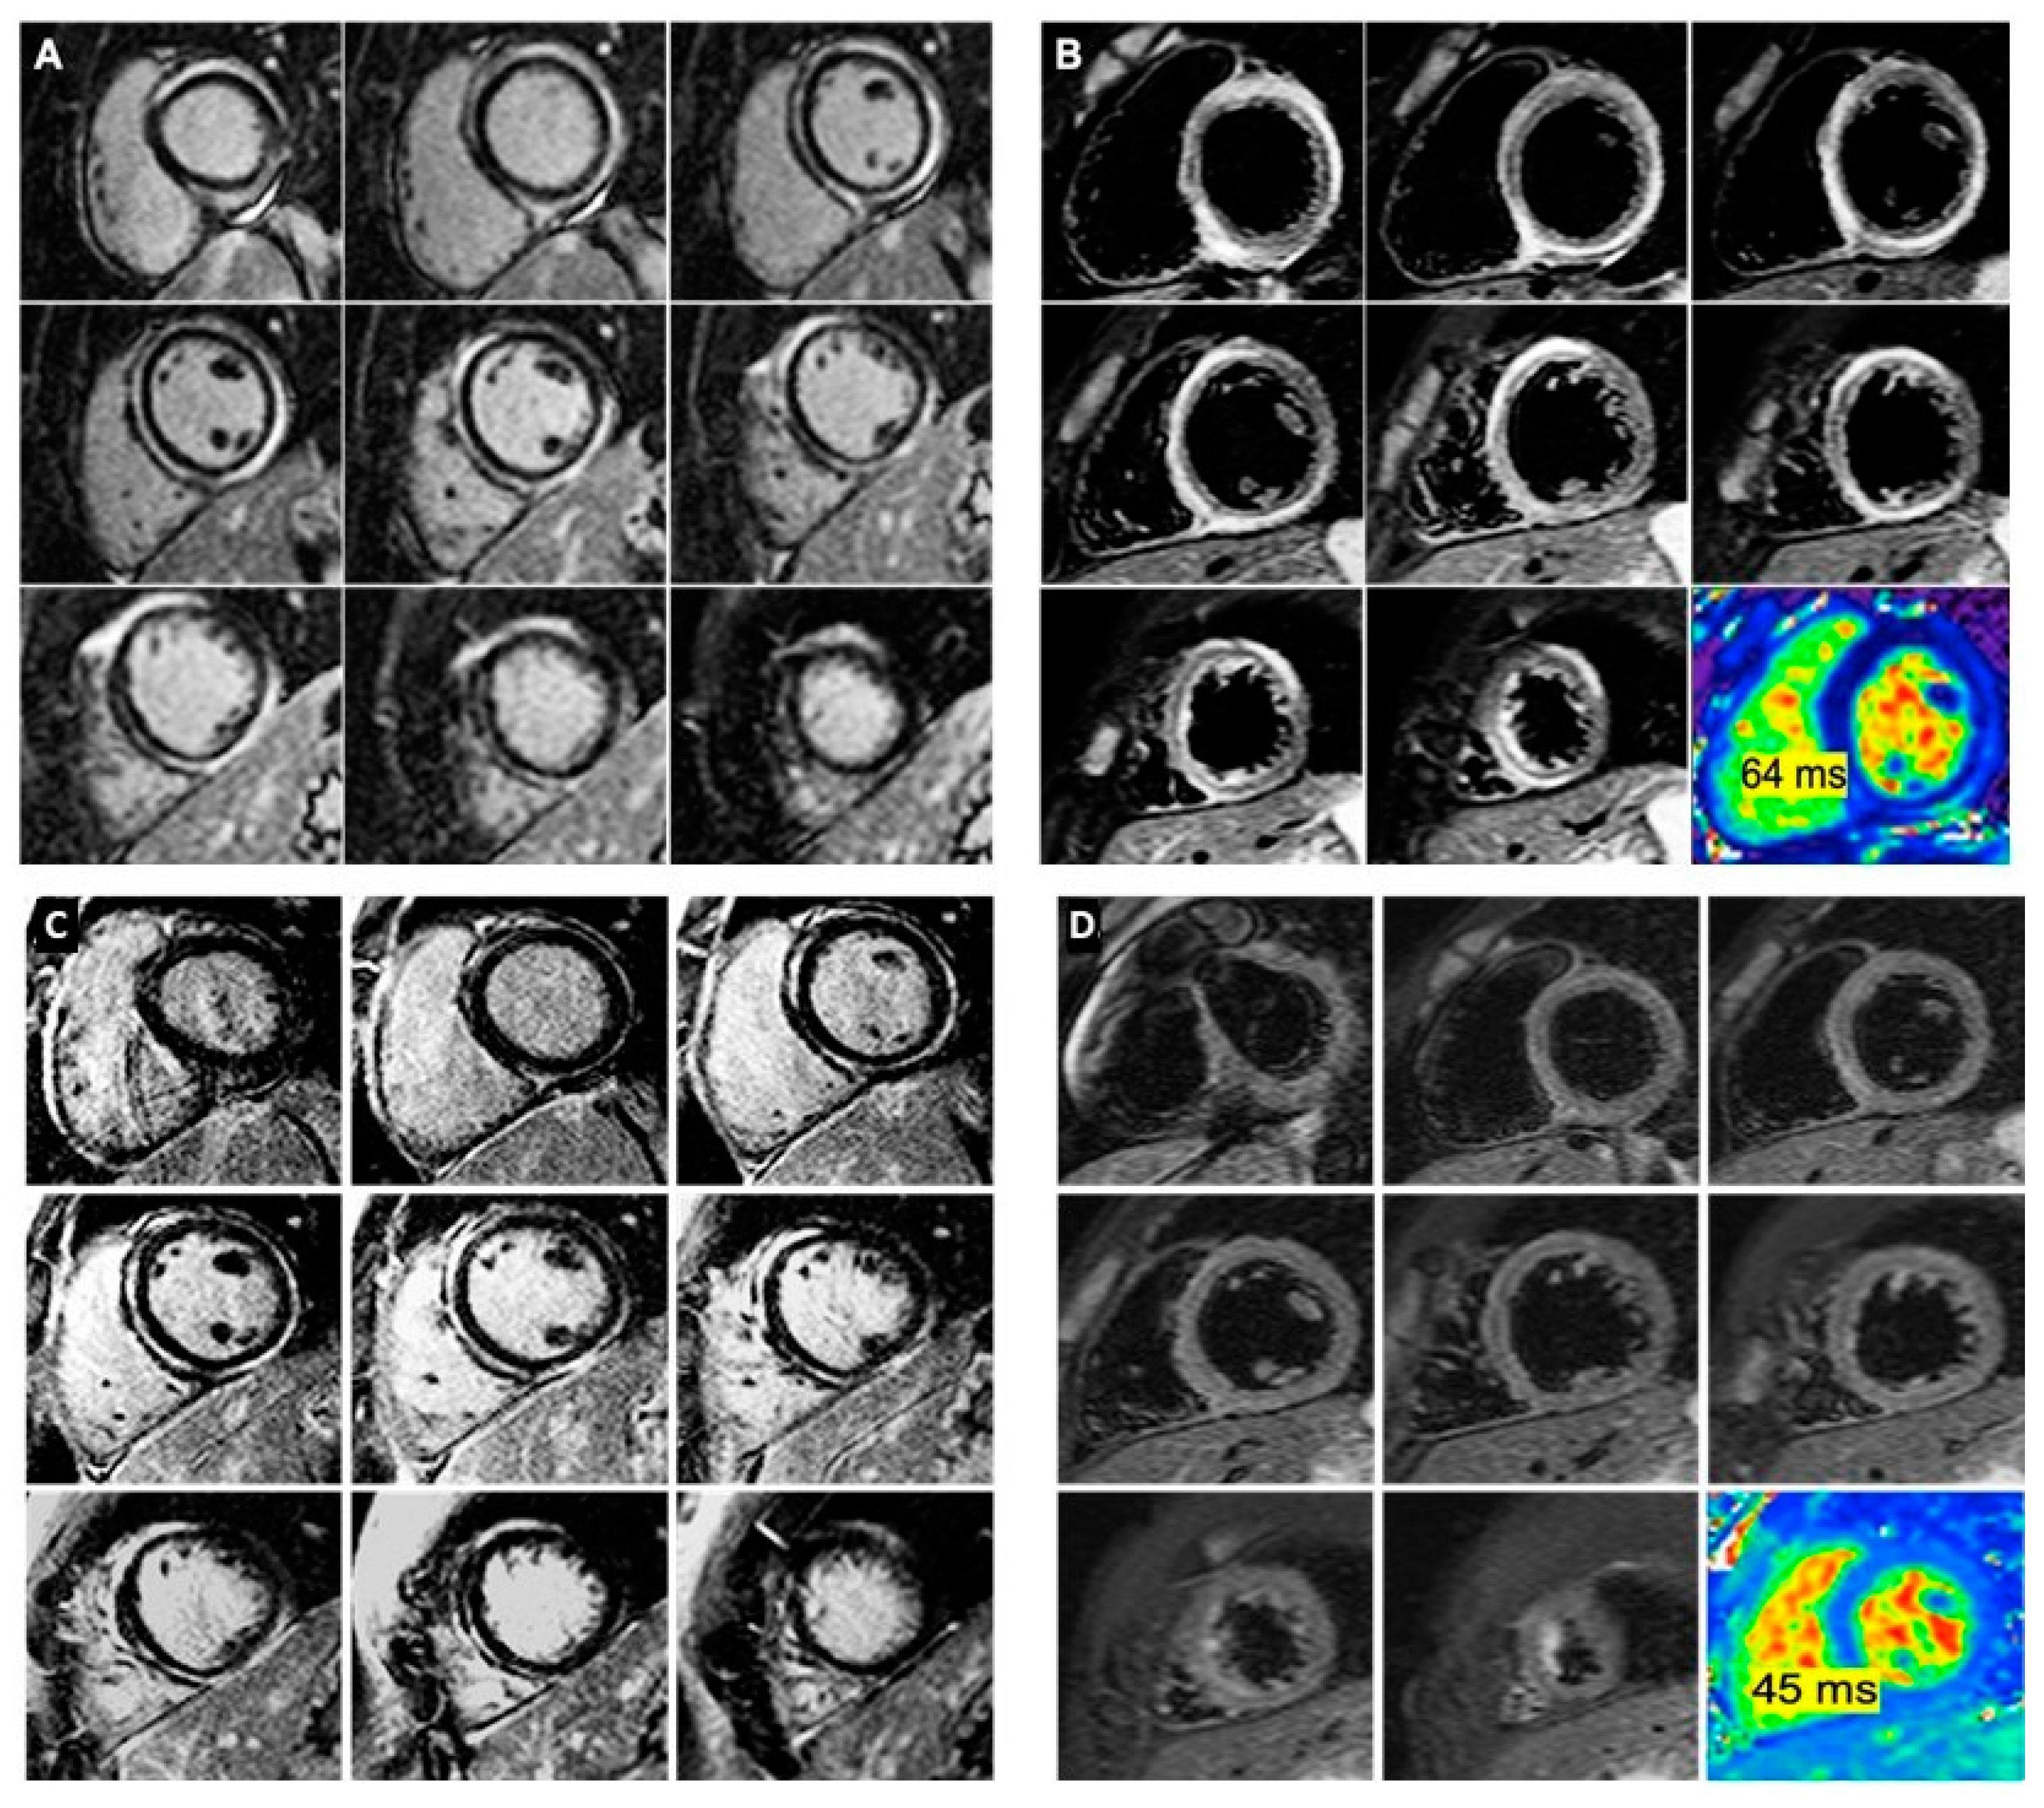

2. Case Reports